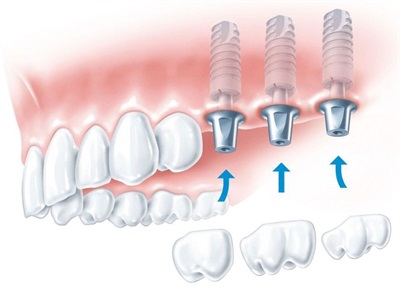

就像天然牙会有牙周炎一样,种植牙也会发炎、生病。种植体周围病包括种植体周围黏膜炎和种植体周围炎。

种植体周围黏膜炎 :局限于种植体周围软组织 ,主要表现为种植体周围牙龈的红肿、出血,是一种可逆性炎症病变,可逆并非指其具有自愈性,而是指通过积极口腔治疗后,种植体周围黏膜炎造成的病损可以被逆转。

种植体周围炎:病变造成骨结合丧失,破坏了种植体周围牙槽骨,主要表现除了种植体周围牙龈的红肿、出血,还有探诊深袋、骨吸收甚至溢脓、松动等表现。